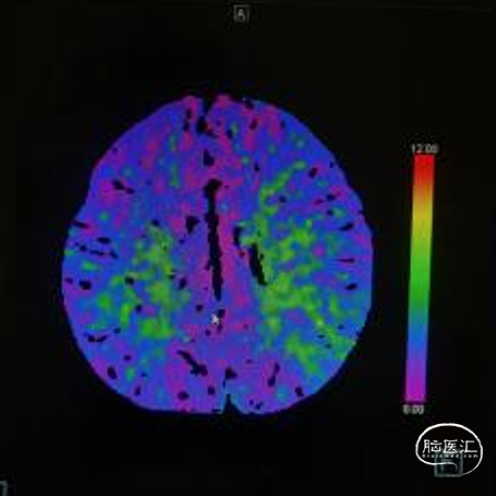

➢术前CTP

MTT